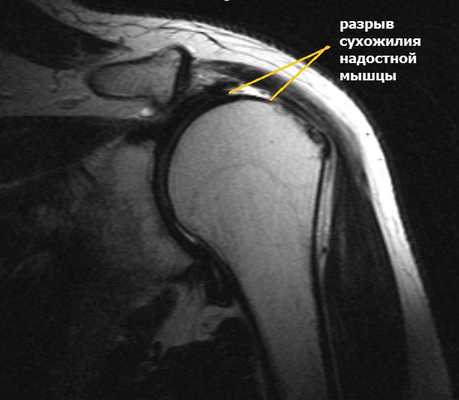

Повреждения вращательной манжеты

К повреждению сухожилий вращательной манжеты могут приводить несколько причин:

- дегенеративные изменения;

- сужение пространства между акромионом и головкой плечевой кости;

- травма;

- хроническая травматизация.

Дегенеративные изменения связаны с нарушением кровообращения сухожилий вращательной манжеты, процессом старения и износом тканей, а также с качественными изменениями коллагеновых волокон в составе сухожилий.

Сужение пространства между акромионом и головкой плечевой кости (импинджмент-синдром) возникает на фоне особого строения акромиального отростка или после получения травмы. Сухожилие надостной мышцы, проходящее в данном пространстве, попадает как бы в тиски и постепенно сдавливается.

Симптомы разрыва вращательной манжеты.

Небольшие разрывы или частичные повреждения могут проходить бессимптомно. Но чаще всего ведущим признаком является боль. При факте травмы боль возникает резко, а при повторяющихся нагрузках она усиливается постепенно и со временем нарастает. Наибольшая интенсивность боли определяется при отведении руки по дуге от 60 0 до 120 0 . Периодически боль усиливается ночью и приводит к нарушению сна.